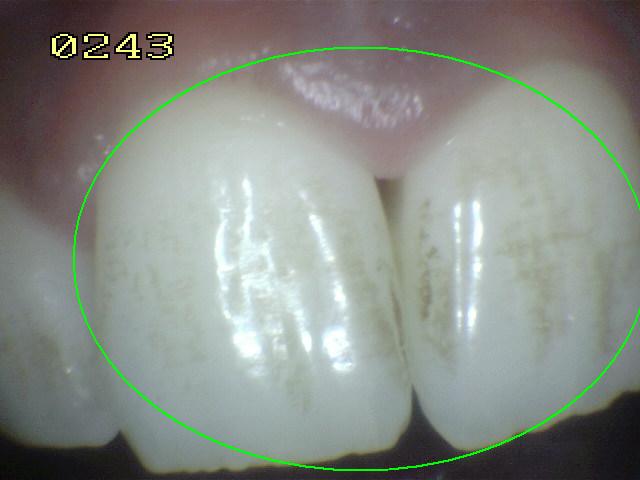

Código 2

(Caries Inicial): Lesión de

caries observada en esmalte en estado húmedo y permanece después de secar

- Cuando la superficie de esmalte se

observa en estado húmedo hay un cambio de color

(mancha blanca o marrón) y después del secado con aire

por 5 segundos se visualiza los rasgos típicos

de la (mancha blanca

/ marrón). Estas lesiones se encuentran tocando el

margen gingival o a un milímetro de este.